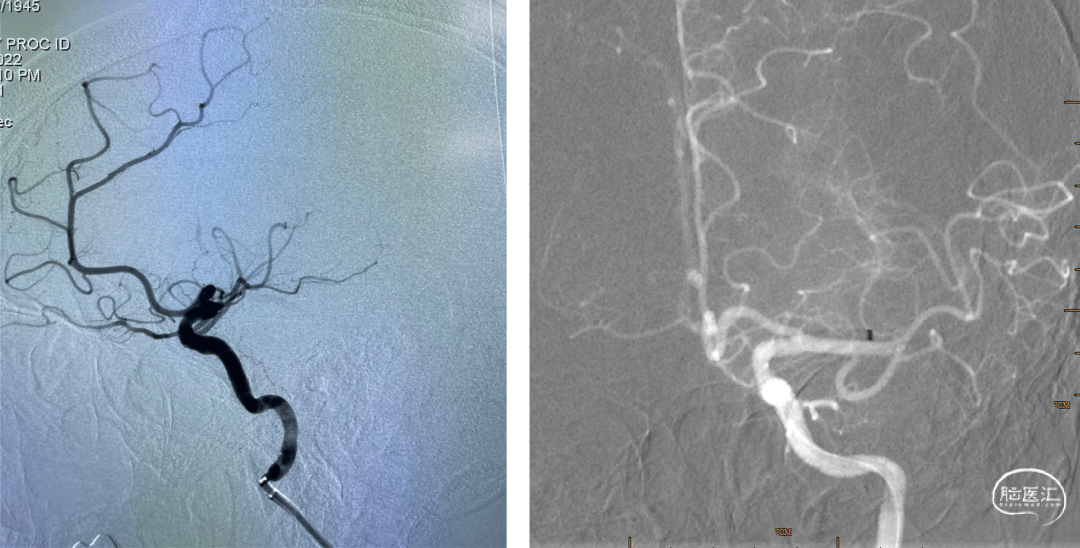

患者老年女性,既往心房颤动病史。因“言语障碍及右侧肢体乏力29小时”入院。患者有明确的大血管闭塞,入院后患者症状加重,MRA提示左侧大脑中动脉闭塞,考虑进展性卒中,患者急诊CTP评估后考虑缺血半暗带大有血管内治疗指征,排除禁忌,拟急诊手术治疗。

患者急性起病,最初起病NIHSS评分3分,最初头颅MRA可见LM1大血管闭塞,但仍有血管残端,结合DWI图像,考虑血栓在分叉部未完全堵塞血管;但后来患者突然加重,考虑侧枝衰竭或血栓位移或二次心源性栓塞可能性大(有房颤病史),计划首先ADAPT抽吸,再Solumbra技术抽拉结合取栓治疗,视情况必要时补充技术。

术后DynaCT,有少量造影剂外渗。予速尿针、白蛋白针、甘露醇针脱水预防脑水肿,阿司匹林肠溶片、抗血小板,强化他汀治疗。